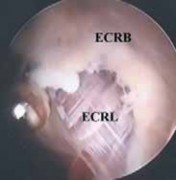

The extensor carpi radialis longus actually originates from the lateral humeral supracondylar ridge, 2 to 3 cm superior to the common extensor tendon, and then passes distally, anterior, and superficial to the ECRB.

Just superficial to the ECRB the extensor carpi radialis longus will come into view ( TECH FIG 2F).

- ### TECH FIG 2 • A. Type I lesion showing synovitis and fraying of the lateral joint capsule. B. Type II lesion showing linear tear of the joint capsule and the extensor carpi radialis brevis (ECRB) tendon near its insertion site.

- C. Type III lesion showing complete avulsion and retraction of the lateral capsule and ECRB tendon. D. Fatty degeneration of the ECRB tendon ( arrow ), which is overlying the ECRL muscle–tendon. E. A 4.5-mm shaver is used for the initial débridement of the ECRB, which is in close proximity to the capitellum ( C ) and radial head ( R ). F. Débridement of the pathologic ECRB tendon and capsule with healthy-appearing extensor carpi radialis longus superficial. G. A 4.0-mm abrader is the final step to decorticate the